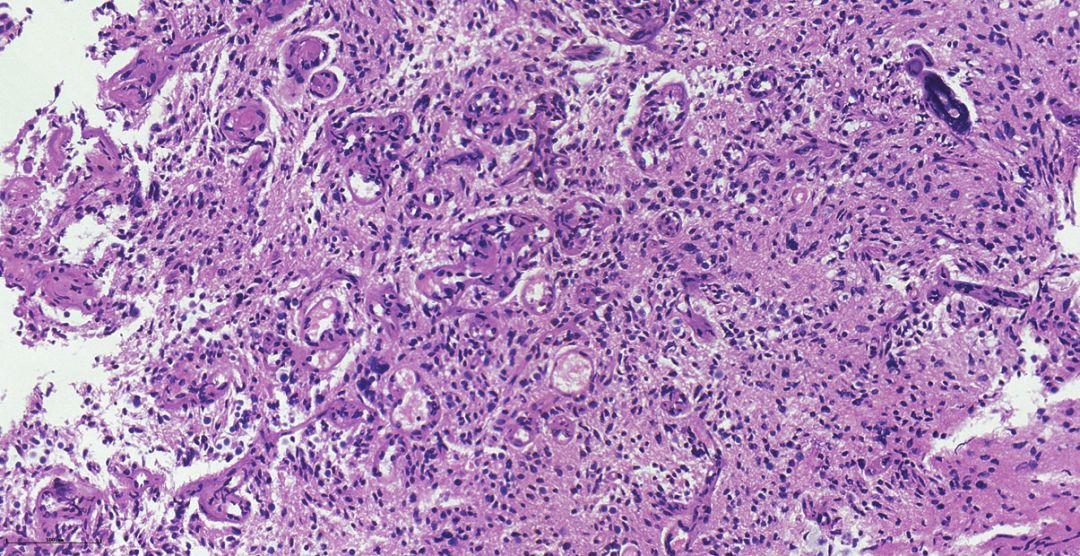

腺样型胶质母细胞瘤1例

图片尺寸470x527